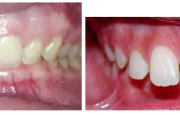

Sügav hambumus

Turritavad ülemised lõikehambad.

Ülemise hambakaare kitsenemine ehk tagumiste hammaste risthambumus.

prognaatne hambumus, ülemised eeshambad on ettepoole alumiste suhtes ja eest

progeenne hambumus; alumised eeshambad on ettepoole ülemiste suhtes;

Normaalse jäävhammaskonna pilt küljelt ja eest vaadatuna.